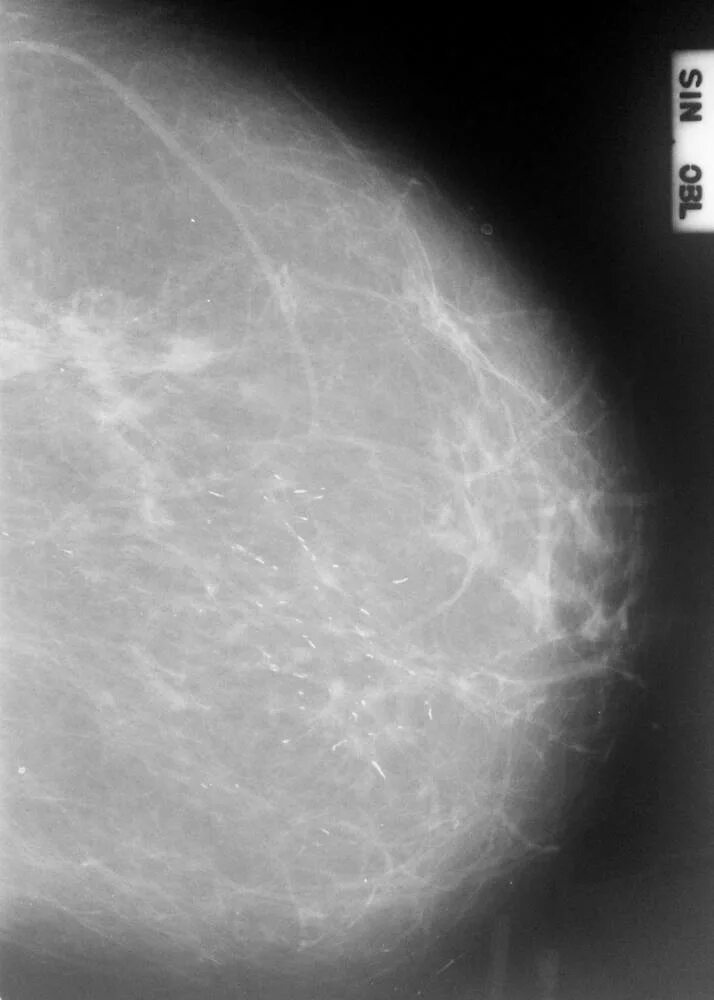

Микрокальцинаты отзывы